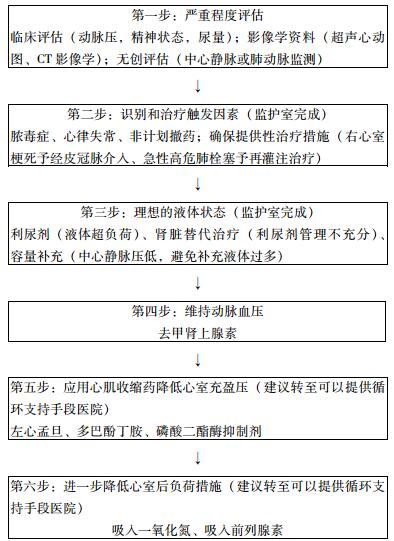

| 图 6 急性右心室衰竭处理流程 |